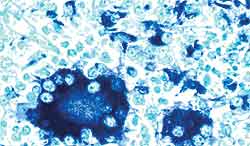

Technique "d'hybridation in situ"- Ganglion mésentérique.

Présence de génome du PCV2 dans le cytoplasme des macrophages et des cellules géantes multinucléés des organes lymphoïdes. |